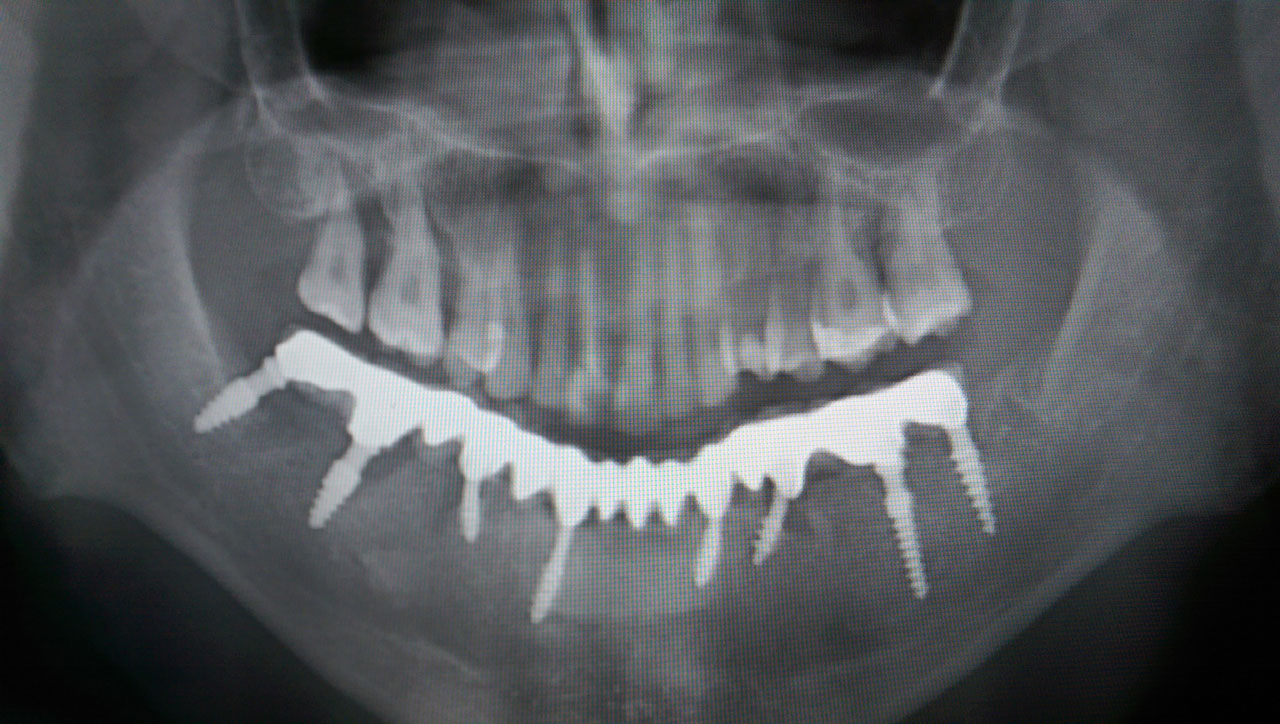

Alsó állcsont teljes rehabilitációja 72 óra alatt

Alsó állcsont teljes rehabilitációja 72 óra alatt, azonnal terhelhető implantátumokkal súlyos paradontitisben szenvedő dohányzó páciens esetében. Az alsó állcsont fogai mind mozogtak az előrehaladott fogágypusztulás miatt.

A fogakat eltávolítottuk, a gyulladt, fertőzött csontot kitakarítottuk, kifertőtlenítettük, majd azonnal implantáltunk.

Svájci, IHDE márkájú, azonnal terhelhető implantátumokat helyzetünk be, és ezekre harmadnapra rögzített, hosszútávú, fémvázas, esztétikus műanyaggal leplezett hidat ragasztottunk be.

Ezt az ideiglenes hidat a sebek gyógyulása miatt használjuk, de tartóssága miatt véglegesként is használható.

A legtöbb esetben, ahogy itt is, 6 hónap múlva porcelán hídra cseréljük, a teljes gyógyulás után.